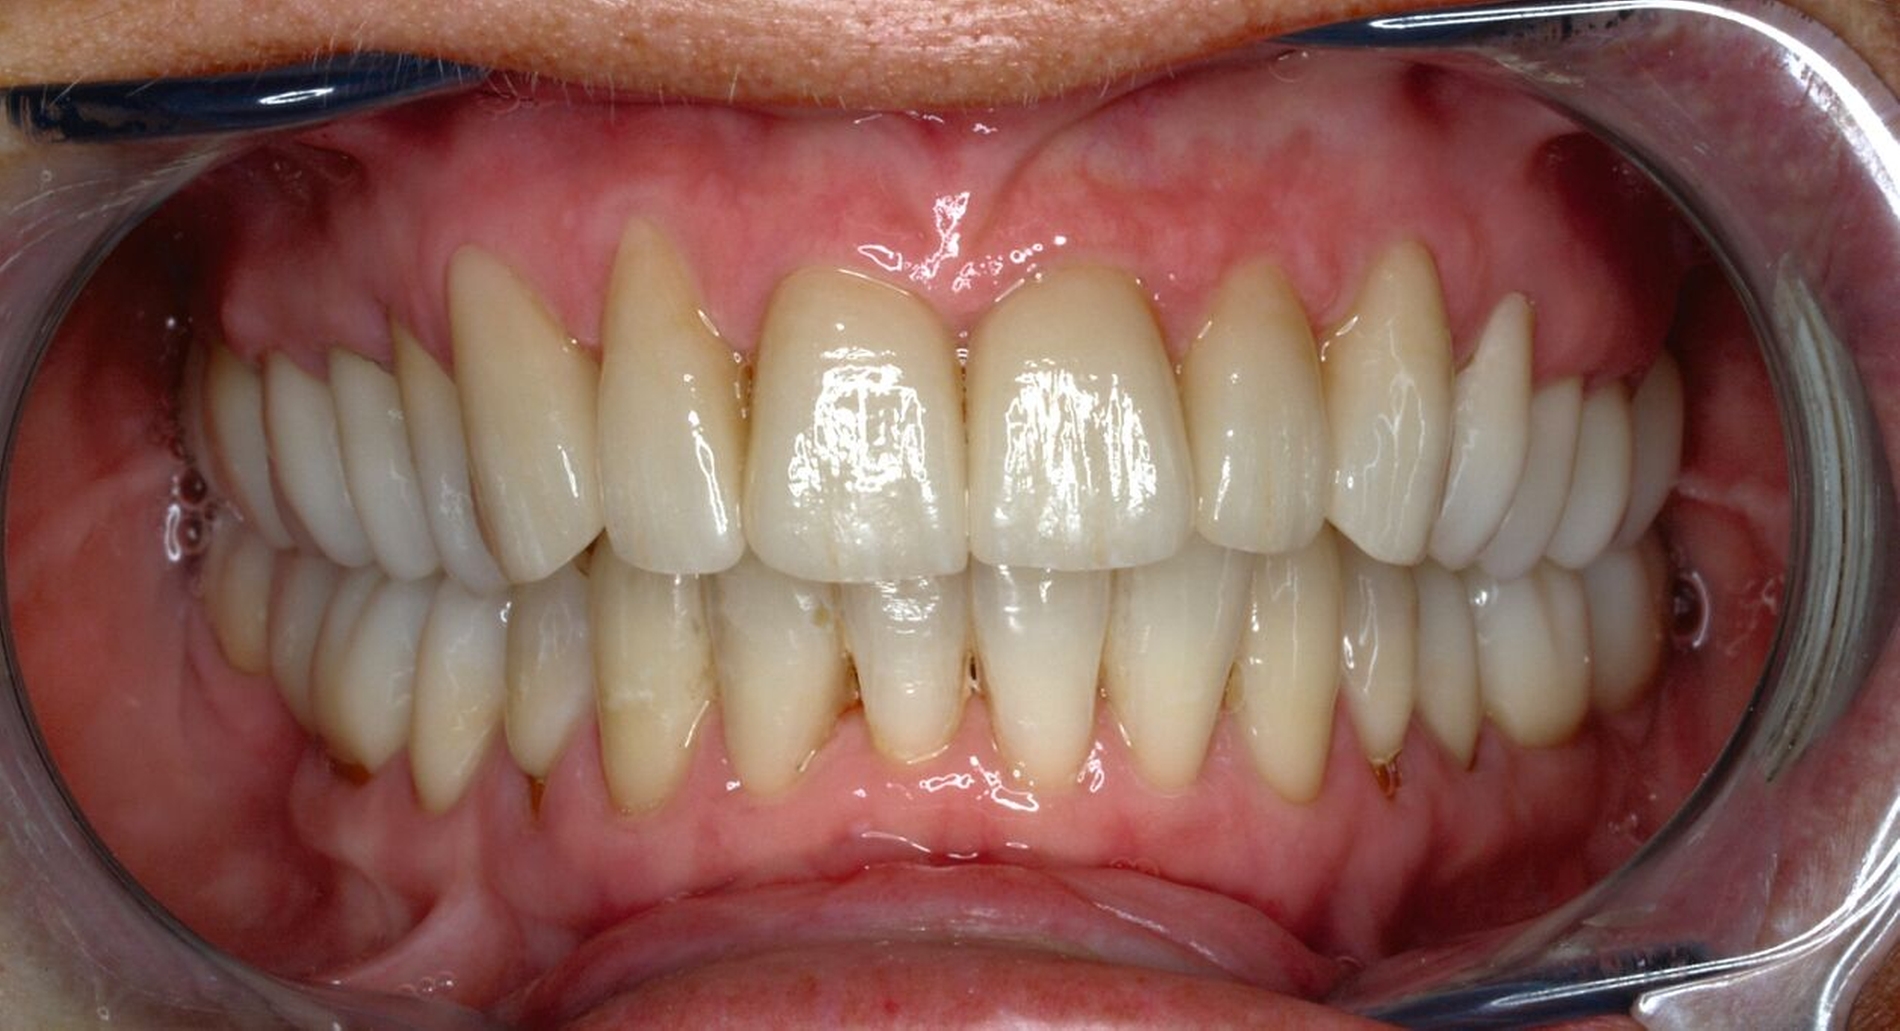

Tabelle 1 zeigt das entsprechende Befundschema mit den Taschentiefen mesial und distal, den Lockerungsgraden und den Sensibilitätsüberprüfungen mittels Kältespray (ViPr). Die Ruheschwebelage wurde mithilfe des Zielinsky-Zirkels auf 2 mm bestimmt. Die Nonokklusion im Seitenzahnbereich konnte auf circa 1,5 mm bemessen werden. Tabelle 2 spiegelt das entsprechende Okklusionsprotokoll wider. Das Okklusionsprofil wird auch in den Abbildungen 3a bis 3c deutlich.

Die anschließenden Verlaufskontrollen zeigten klinisch stabile Verhältnisse. Der prothetische Behandlungsaufwand betrug etwa acht Monate inklusive Planung, Begutachtung, Durchführung und Inkorporation des Zahnersatzes. In den Folgeterminen wurde der Patientin noch eine Aufbissschiene für den Unterkiefer eingegliedert, um Schäden durch etwaigen Schlafbruxismus vorzubeugen [Macedo et al., 2007]. Für die Nachsorge empfiehlt sich ein halbjährliches Kontrollintervall. Die erfolgte Okklusionskorrektur im Seitenzahnbereich wird in Abbildung 11 deutlich.